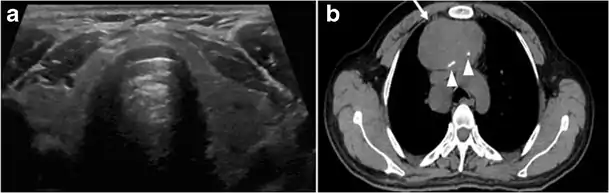

Goiter

A goiter is an abnormal thyroid gland proliferation that manifests as multi-nodular, uni-nodular, or non-nodular diffuse glandular enlargement. A goiter is formed of solid matrix, colloid cysts, blood products, calcification, and fibrosis, and this heterogeneity may lead to variable appearances on a CT scan (Figs. 13, 1414 and and15)15). US is more sensitive in evaluating thyroid nodules within a goiter; however, a symptomatic goiter may require surgical treatment with total thyroidectomy, and in this case CT plays an additional role in preoperative evaluation. Specific aspects for examination on a CT scan during the preoperative evaluation for goiter include extension, mass effect, and suspicious features of malignancy.[1]

Malignancy can coexist within the goiter and a CT scan may give a clue if there are abnormal cervical lymph nodes and/or signs of invasion. Retrosternal extension (Fig. 15) could affect the surgical approach, as a lower extent may require a partial or total sternotomy to facilitate complete resection. Therefore, the distance of the retrosternal extent from the sternal notch should be measured on a sagittal image.[1]

The interpreting radiologist should describe the mass effect, detailing its degree and direction of displacement of central structures, including the trachea, oesophagus, larynx, and pharynx. Attention should be directed to the upper extent of the goiter and structures immediately surrounding the thyroid gland, including the neuro-vascular structures, retropharyngeal space, and pre-vertebral space. The reporting radiologist should evaluate the vocal cords for symmetry and signs of vocal cord palsy.[1]